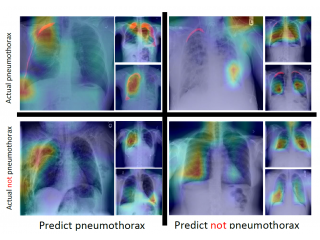

No longer a Black Box––AI Makes Sense, too! –– Discuss Explainable AINo longer a Black Box––AI Makes Sense, too! –– Discuss Explainable AIDeep learning can solve many problems and be used in many tasks, such as image classification, target detection, image segmentation...etc. What does the DL model learn during training? What does it see in the images to base its judgment on? Explainable AI is the answer to such questions.

No longer a Black Box––AI Makes Sense, too! –– Discuss Explainable AINo longer a Black Box––AI Makes Sense, too! –– Discuss Explainable AIDeep learning can solve many problems and be used in many tasks, such as image classification, target detection, image segmentation...etc. What does the DL model learn during training? What does it see in the images to base its judgment on? Explainable AI is the answer to such questions. -